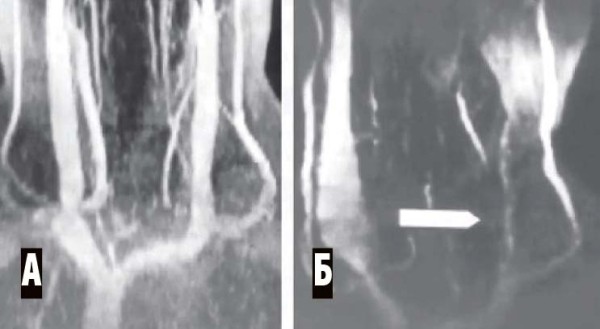

Магнитно-резонансная венография (аппараты МРТ имеют специальную программу для такого исследования). Исследуются синусы головного мозга, а также вены шеи. Всегда сравниваются правая и левая стороны (см. рис. 4, 5).

Рисунок 4. Рентгенограмма синусов головного мозга в норме. 1 — верхний сагиттальный синус, 2 — нижний сагиттальный синус, 3 — поперечный синус, 4 — сигмовидный синус.

Рисунок 5. МР-венография при тромбозе синусов. А — левая сторона, обнаружено отсутствие сигнала от левых поперечного и сигмовидного синусов (признак тромбоза). Б — правая сторона, кровоток по синусам в норме.

МР-венография брахиоцефальных вен (см. рис. 6).

Рисунок 6. МР-венограмма. Мышечная компрессия внутренней яремной вены. А — брахиоцефальные вены в норме, Б — сдавление левой внутренней яремной вены гипертрофированными нижними шейными мышцами (уровень сдавления показан стрелкой). Противоположная внутренняя яремная вена компенсаторно расширена.